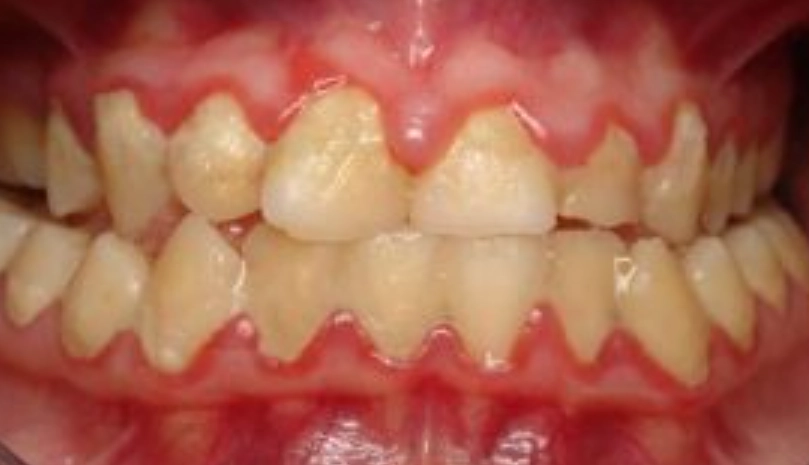

3. 忽略了最重要的區域:牙縫

牙刷的刷毛再細,也無法進入牙縫深處進行有效清潔。牙縫是牙菌斑和食物殘渣的「高級住宅區」。如果你只用牙刷,等於只清潔了牙齒表面的60%。牙線或牙間刷才是清潔牙縫的專屬工具。很多人說用牙線會流血,那正是牙齦發炎的訊號,越不用,發炎越嚴重,形成惡性循環。

個人經驗分享: 我曾經幫一位自認刷牙很認真的患者檢查,他後牙的鄰接面(牙齒彼此緊靠的面)滿是牙菌斑,甚至開始蛀牙,但他渾然不覺。因為那些地方從鏡子裡根本看不見,舌頭也舔不到。這說明了「自我感覺乾淨」和「實際乾淨」之間存在巨大落差。